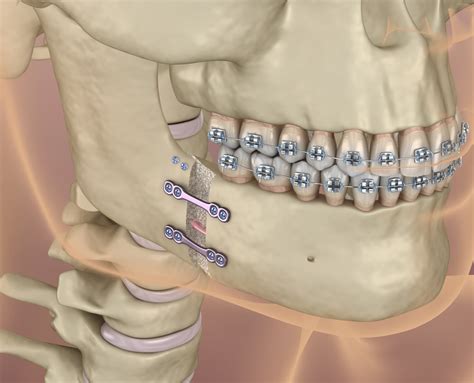

16+ Wiring Jaw Shut Surgery - MarcelWillum